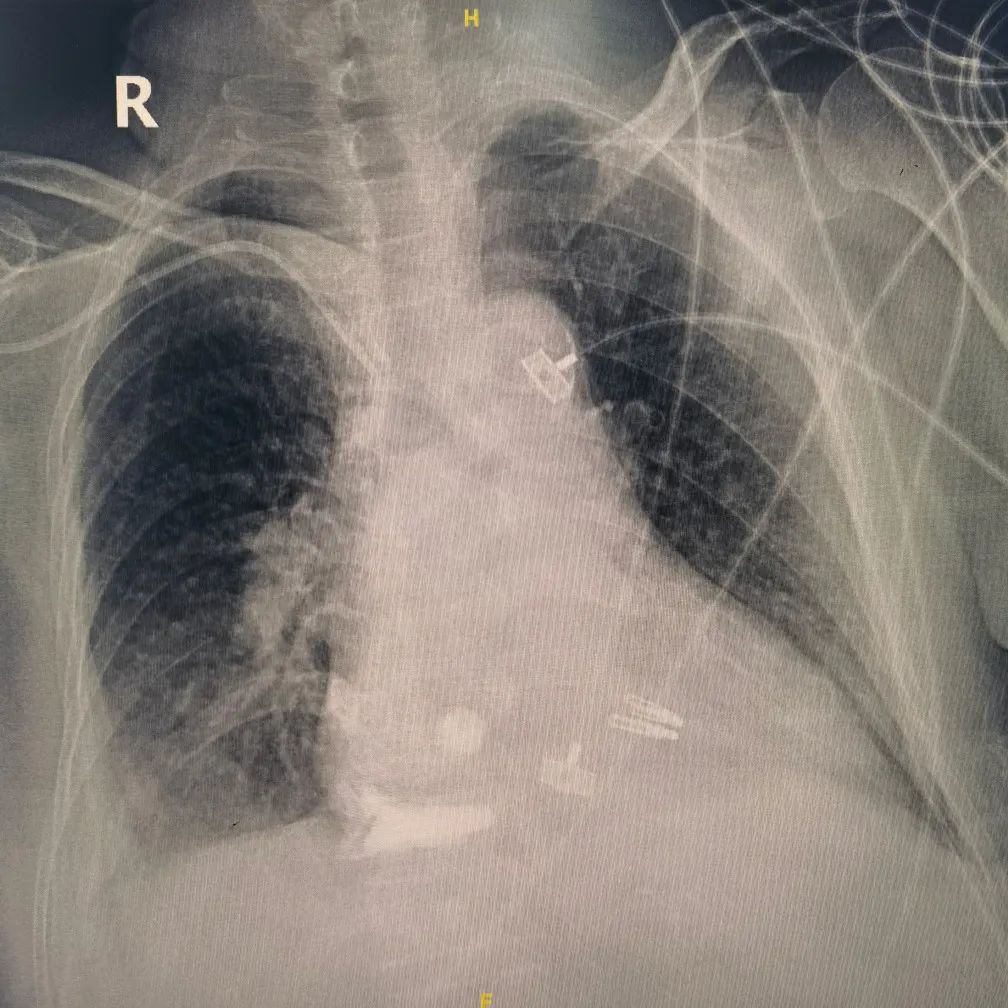

术后继续予冠心病二级预防、利尿、升压、改善心功能等对症支持治疗。因存在急性心肌梗死后机械性并发症,二尖瓣重度反流,床旁胸片提示双肺渗出,循环不稳定,氧饱和度差,于重症监护病房行气管插管,呼吸机辅助呼吸,并床旁CRRT肾脏替代治疗以维持内环境稳态。但患者心功能仍进一步恶化,大剂量血管活性药物泵入仍无法维持血压,遂予床旁植入VA-ECMO。

术前床边胸片

术后48h床边胸片